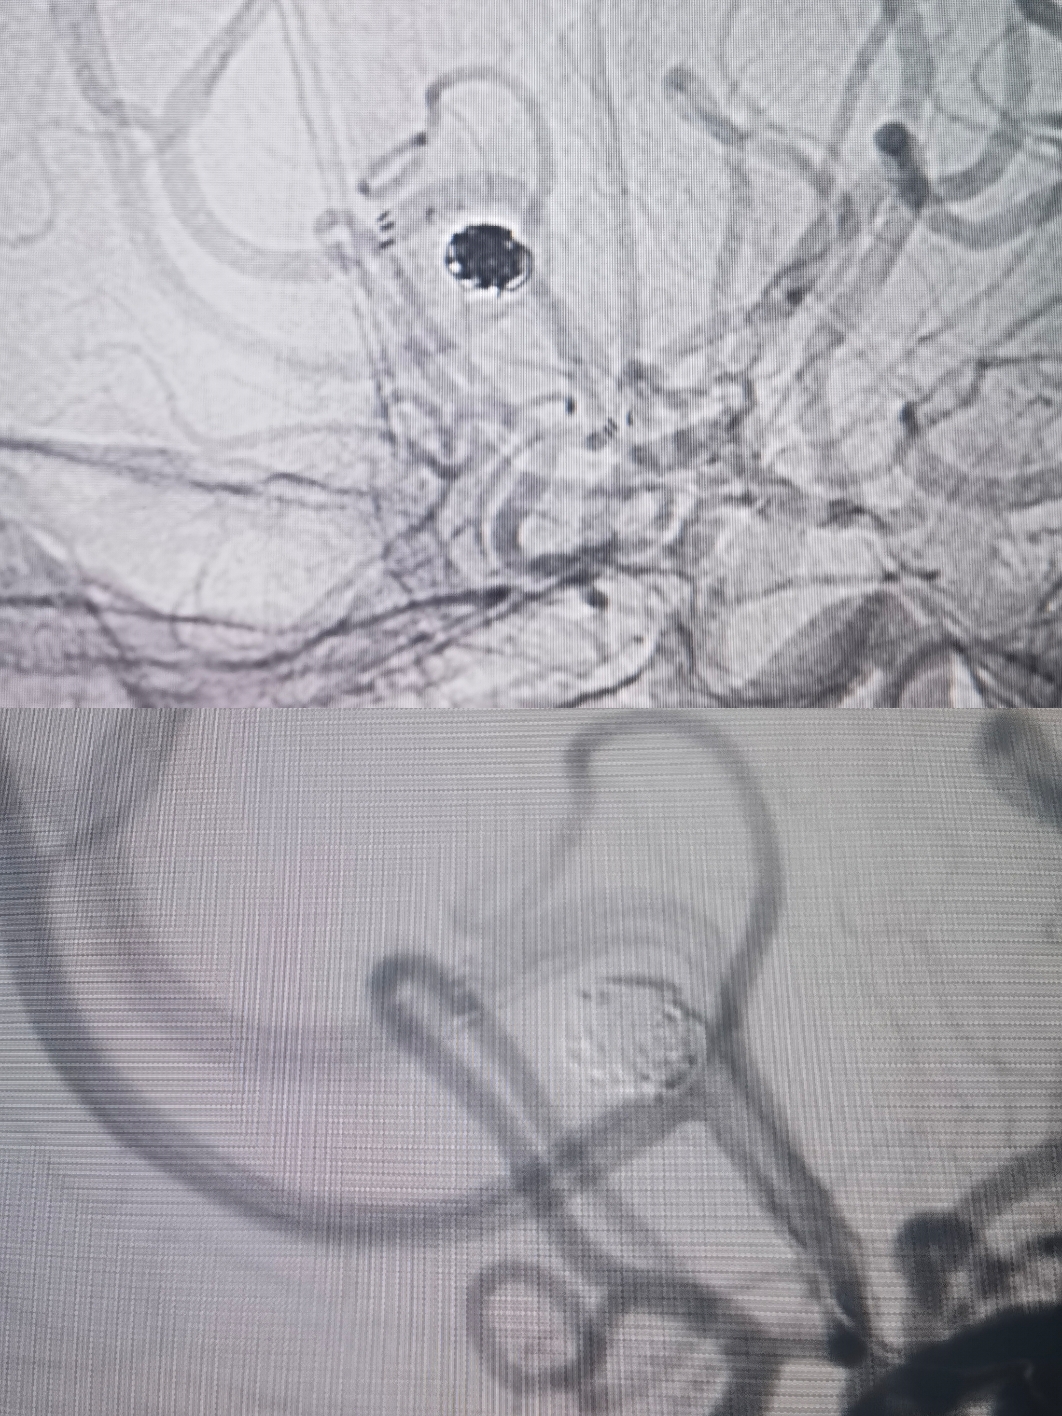

双微管到达A2后,指引导管造影无法看到动脉瘤。经微管造影及路途,支架导管和栓塞微导管分别到位。选用开环支架穹窿效应缩窄瘤颈,保护对侧大脑前。

栓塞术后情况

术后重建情况